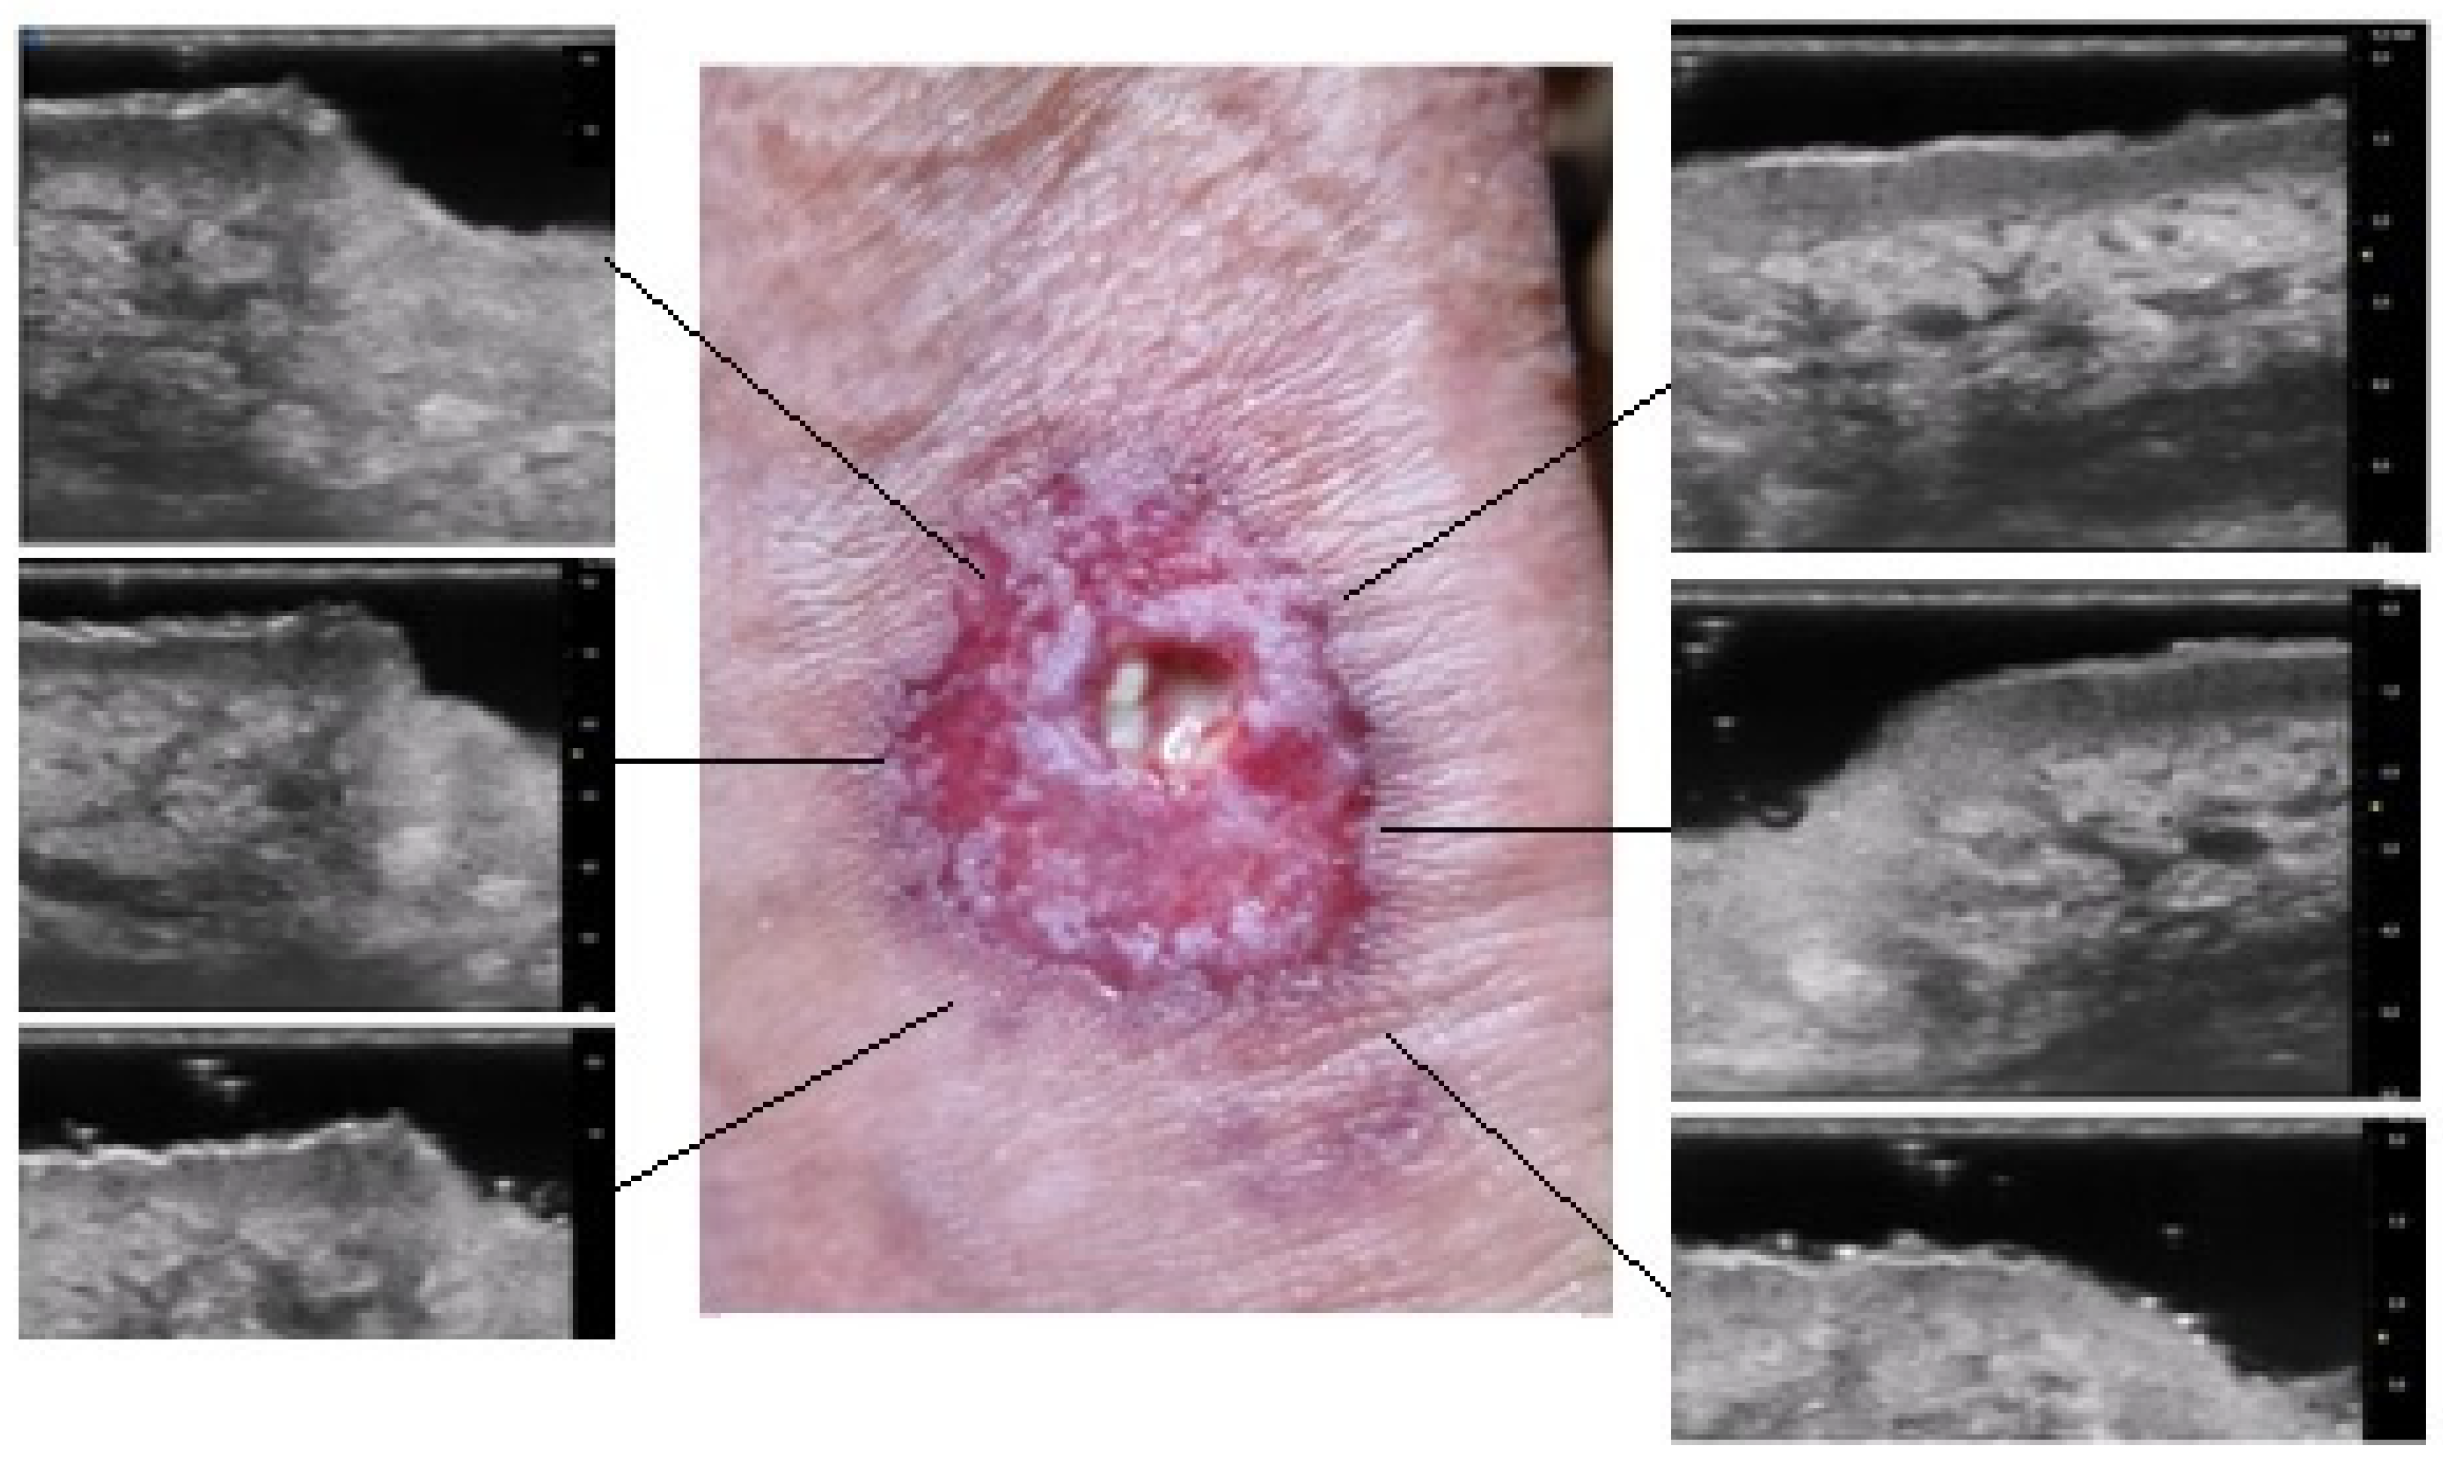

The results obtained by our investigation revealed some UHFUS differences between the inflammatory and non-inflammatory phases. At T0, oval hyperechoic structures, that statistically significantly decreased in T1, were identified in the papillary and reticular dermis (p-value < 0.05) (Figure 4 and Figure 5).

Figure 4.

Patient affected by ulcerative Pyoderma Gangrenosum (PG) of the calf during the inflammatory phase: clinical aspect of the wound and its Ultra-High Frequency UltraSound (UHFUS) correlates.

Figure 5.

Patient affected by ulcerative Pyoderma Gangrenosum (PG) of the calf during the non-inflammatory phase: clinical aspect of the wound and its Ultra-High Frequency UltraSound (UHFUS) correlates.